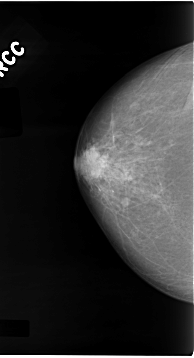

C_0074_1.LEFT_CC

LEFT_CC LINES 4704 PIXELS_PER_LINE 2472 BITS_PER_PIXEL 12 RESOLUTION 50 OVERLAY

FILE: C_0074_1.LEFT_CC.OVERLAY

TOTAL_ABNORMALITIES 1

ABNORMALITY 1

LESION_TYPE MASS SHAPE IRREGULAR MARGINS SPICULATED

ASSESSMENT 5

SUBTLETY 5

PATHOLOGY MALIGNANT